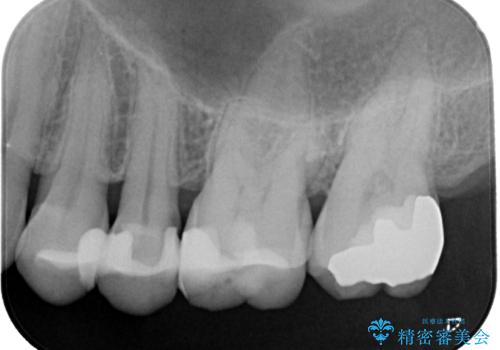

- 奥歯がかけてしまい、しみるようになったとのことで来院された患者様です。

上顎奥の粘膜に近い部分で、つめものの下には大きく虫歯が広がっていました。

虫歯をしっかりと取り除き、ゴールドインレーにて修復することとしました。

ゴールドインレーは銀歯のインレーやセラミックインレーと比べ、「技工操作の精度が高く、適合が著しく良い」というメリットがあります。特に上の奥歯は歯科医師の操作が行いにくいため、「適合の良さ」は再治療のリスクを防ぐ上でとても重要な要素となります。